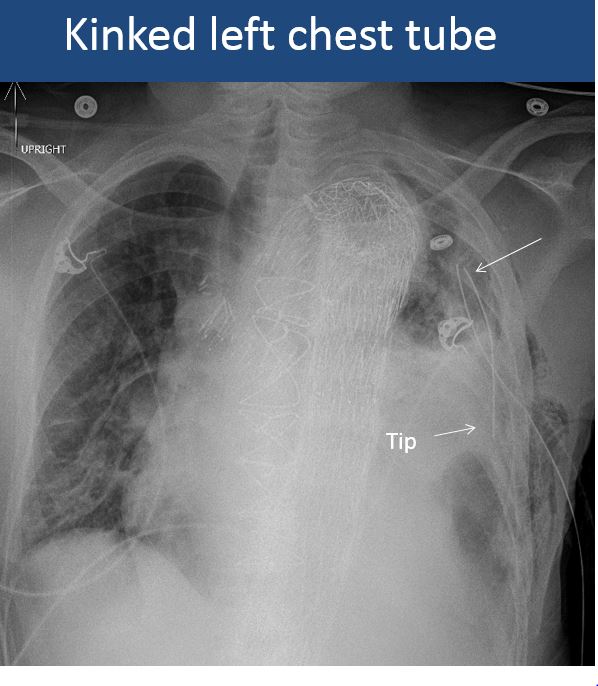

There is a chest tube in place and the side port of the chest tube is outside of the bony thorax or the tube is otherwise abnormally positioned. [Yes/No]